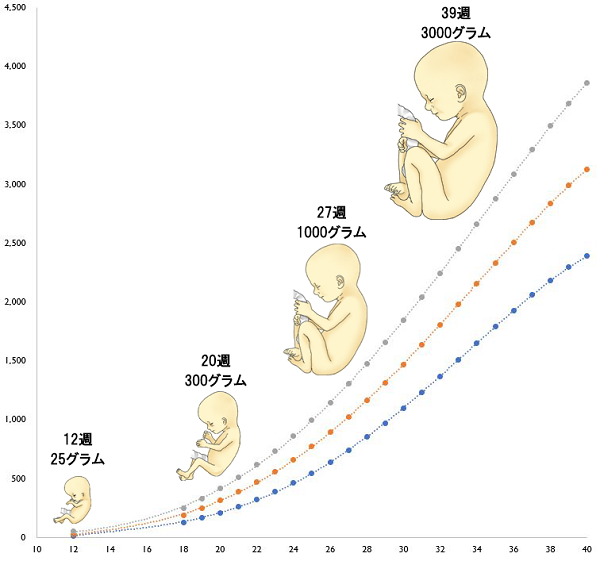

母子手帳「胎児発育曲線 新生児の成長曲線 」の見方と活用法-おむつのムーニー 公式 ユニ・チャーム。

医師監修 胎児の発育曲線 成長曲線 とは?どのように見ればいいの?ゼクシィBaby。

胎児発育曲線』とは?週ごとの発育の目安を助産師が解説◎ - 株式会社エバーセンス。

胎児発育曲線』とは?週ごとの発育の目安を助産師が解説◎ - 株式会社エバーセンス。

胎児発育曲線の±2.0SDの意味は?エコー写真に学ぶ統計学 - 日常を少し掘り下げてみる。

医師監修 おなかの赤ちゃんの発育は順調? 「胎児発育曲線」とはトモニテ。

胎児発育曲線の±2.0SDの意味は?エコー写真に学ぶ統計学 - 日常を少し掘り下げてみる。

母子手帳「胎児発育曲線 新生児の成長曲線 」の見方と活用法-おむつのムーニー 公式 ユニ・チャーム。